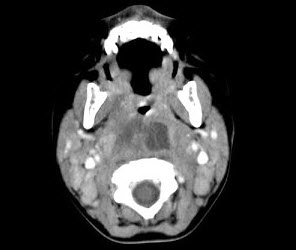

[多选题] 10个月大的婴儿,发热,曾患中耳炎,CT扫描如图所示,正确的描述或诊断是()A . 咽后壁软组织肿胀B . 其内密度不均C . 颈椎骨质未见明显异常D . 咽后壁脓肿E . 咽后壁寒性脓肿